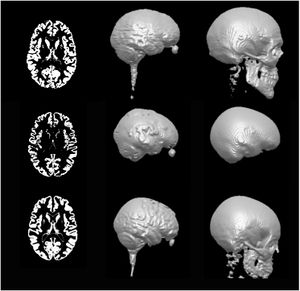

A Novel Procedure for Rapid Imaging of Adult Mouse Brains with MicroCT using Iodine-Based Contrast

Publication: PLoS One. 2015 Nov 16;10(11):e0142974. PMID: 26571123 | PDF Authors: Anderson R, Maga AM. Institution: Center for Developmental Biology and Regenerative Medicine, Seattle Children's Research Institute, Seattle, WA, USA. Background/Purpose: High-resolution Magnetic Resonance Imaging (MRI) has been the primary modality for obtaining 3D cross-sectional anatomical information in animals for soft tissue, particularly brain. However, costs associated with MRI can be considerably high for large phenotypic screens for gross differences in the structure of the brain due to pathology and/or experimental manipulations. MicroCT (mCT), especially benchtop mCT, is becoming a common laboratory equipment with throughput rates equal or faster than any form of high-resolution MRI at lower costs. Here we explore adapting previously developed contrast based mCT to image adult mouse brains in-situ. We show that 2% weight per volume (w/v) iodine-potassium iodide solution can be successfully used to image adult mouse brains within 48 hours post-mortem when a structural support matrix is used. We demonstrate that hydrogel can be effectively used as a perfusant, which limits the tissue shrinkage due to iodine. Funding:

|

A. A representative high-resolution MRI scan of an age matched C57BL/6J displaying the brain and the mCT overlay (yellow outline) from [21]. B. Equivalent cross sections from five females that constitute the Group A (Hg perfusion) after 48h of staining in 2% I2KI. C. One individual that constitutes Group B (PFA perfusion) after 48h of staining in 2% I2KI. D-F: Heatmaps showing the difference in the obtained segmentations with respect to the reference MRI atlas constructed from [21,22]. To remove volumetric differences due to sex and age, we isometrically scaled our segmented brains to match the volume of the reference MRI atlas. Root mean square (RMS) errors are calculated after the scaling. D: Comparison of our Group A mCT atlas. RMS = 0.128 mm. E: Comparison of individuals of Group A. RMS values are 0.172 mm, 0.143 mm, 0.156 mm, 0.142 mm, 0.196 mm respectively. F: Comparison of Group B. RMS = 0.232 mm. All comparisons are rendered on MRI reference atlas. Grey area in the heat map indicate regions of large difference (>0.5 mm) either due to extreme shrinkage or difference in segmentation. Using this outline as the boundary, stained brains were interactively segmented using the editor module of 3D Slicer. |